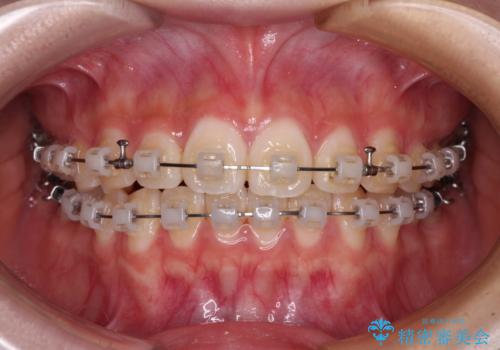

- 矯正装置

- クリアブラケット

- 治療期間

- 11ヶ月

- 上下前歯のねじれを気にして来院された患者様です。

ワイヤー矯正でもマウスピース矯正でも対応可能でしたが、マウスピース矯正の自己管理が面倒であること、上顎前歯の捻転が著しいことから、ワイヤー矯正での治療を希望されました。